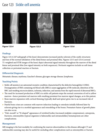

An anteroposterior view of the pelvis

shows flaring of the metaphyseal regions of

the proximal femurs and numerous osteochondromas

arising from the right iliac crest, pubic bones, and proximal right femur (arrows).

Axial CT through upper pelvis - Large right exostosis with soft tissue mass.

AP radiograph of knee - multiple osteochondromas arising from femur and fibula.

DIAGNOSIS: Multiple hereditary exostosis

AD disorder age 10-20s

Signs of malignant transformation - Growth of previous stable exostosis, new or increasing calcifications, new bony erosion

Associated with chondrosarcoma